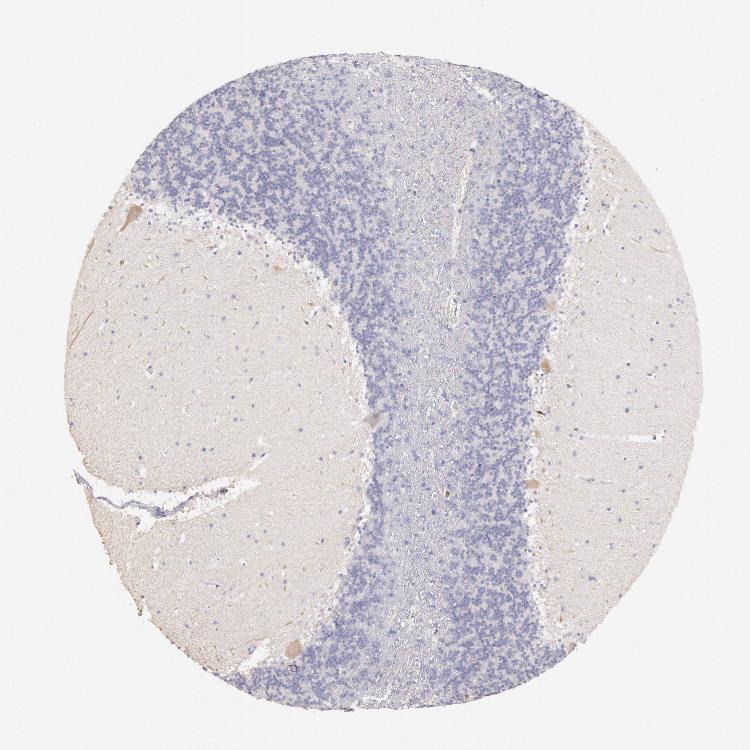

BRAIN CEREBELLUM Show tissue menu

CEREBELLUM - Expression summary

CEREBELLUM - Antibody stainingi

Antibody staining in the annotated cell types in the current human tissue is reported as not detected, low, medium, or high, based on conventional immunohistochemistry profiling in selected tissues. This score is based on the combination of the staining intensity and fraction of stained cells.

Each image is clickable and will lead to virtual microscopy that enables deeper exploration of all samples and also displays staining intensity scores, fraction scores and subcellular localization as well as patient and tissue information for each sample.

Antibody HPA001333Antibody CAB034046

Purkinje cells LowLow

Cells in granular layer Not detectedNot detected

Cells in molecular layer Not detectedNot detected